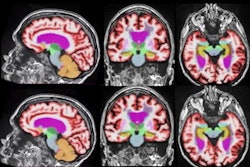

Researchers and public health experts have been grappling to explain "long COVID," a set of symptoms that persist in individuals long after they've recovered from the acute phase of COVID-19. A new study illustrates the challenge in understanding the condition -- individuals who reported long-term symptoms did not have any differences from normal controls on brain imaging scans.